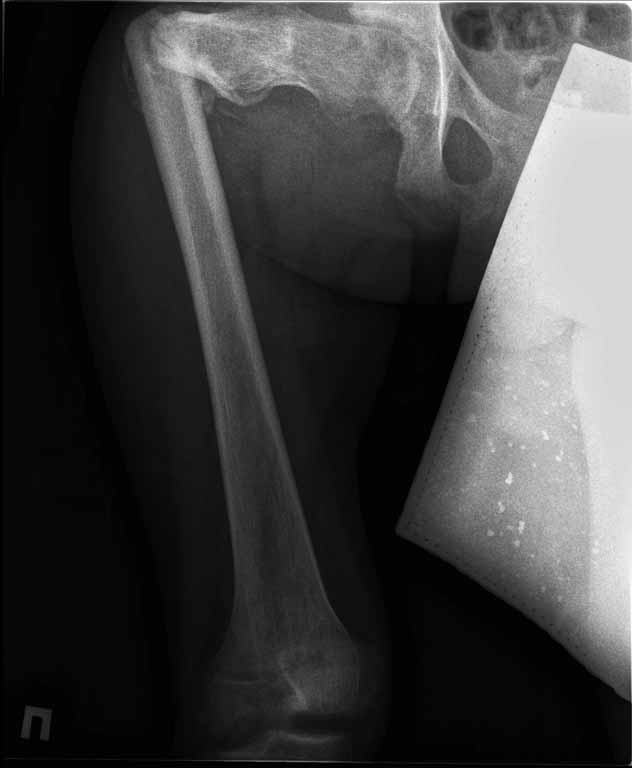

Пациенту 22 года. Травма в июле 2010г, лечился в районной больнице. К нам попал в апреле 2011г.Тяжелая сочетанная травма (29.07.2010): тупая травма живота с повреждением внутренних органов. Закрытая травма грудной клетки с переломом ребер. Пневмоторакс справа. Тяжёлая позвоночно-спинномозговая травма. Закрытый осложнённый переломо-вывих С5 позвонка. Верхний парапарез, нижняя параплегия, нарушение функции тазовых органов по типу недержания. Цекостома. Пролежень левой ягодичной области. Неправильно консолидированные переломы верхних третей обеих бедер. Застарелый вывих левого бедра.Осложнение: Поддиафрагамльный абсесс слева, забрюшинного пространства. Свищ желудка и ободочной кишки. Синегнойный сепсис. Двухстороняя пневмония. Но это уже анамнез.Пациент был неоднократно оперирован на органах брюшной полости и осложнениями с ними связанными.

В ягодичной области слева глубокий пролежень размером 2х2см, дном является вывихнутая головка бедра. Неврологически в нижних конечностях динамика положительная, появились движения в правой стопе, чувствительность в стопах.По переломам бедер: подвижности в местах переломов нет, снимки высылаю.

Уважаемые коллеги, помогите определиться с оптимальной тактикой в лечении перелома бедер. Степень оснащенности у нас достаточная (аппараты, штифты, пластины, ЭОП).

Планирую начать с правого бедра, ЧКО таза (передняя рама) с фиксацией бедра. О/клазия места перелома правого бедра и устранение грубых смещений в аппарате. окончательно можно оставить и в аппарате. Далее аппаратное устранение вывиха левого бедра.